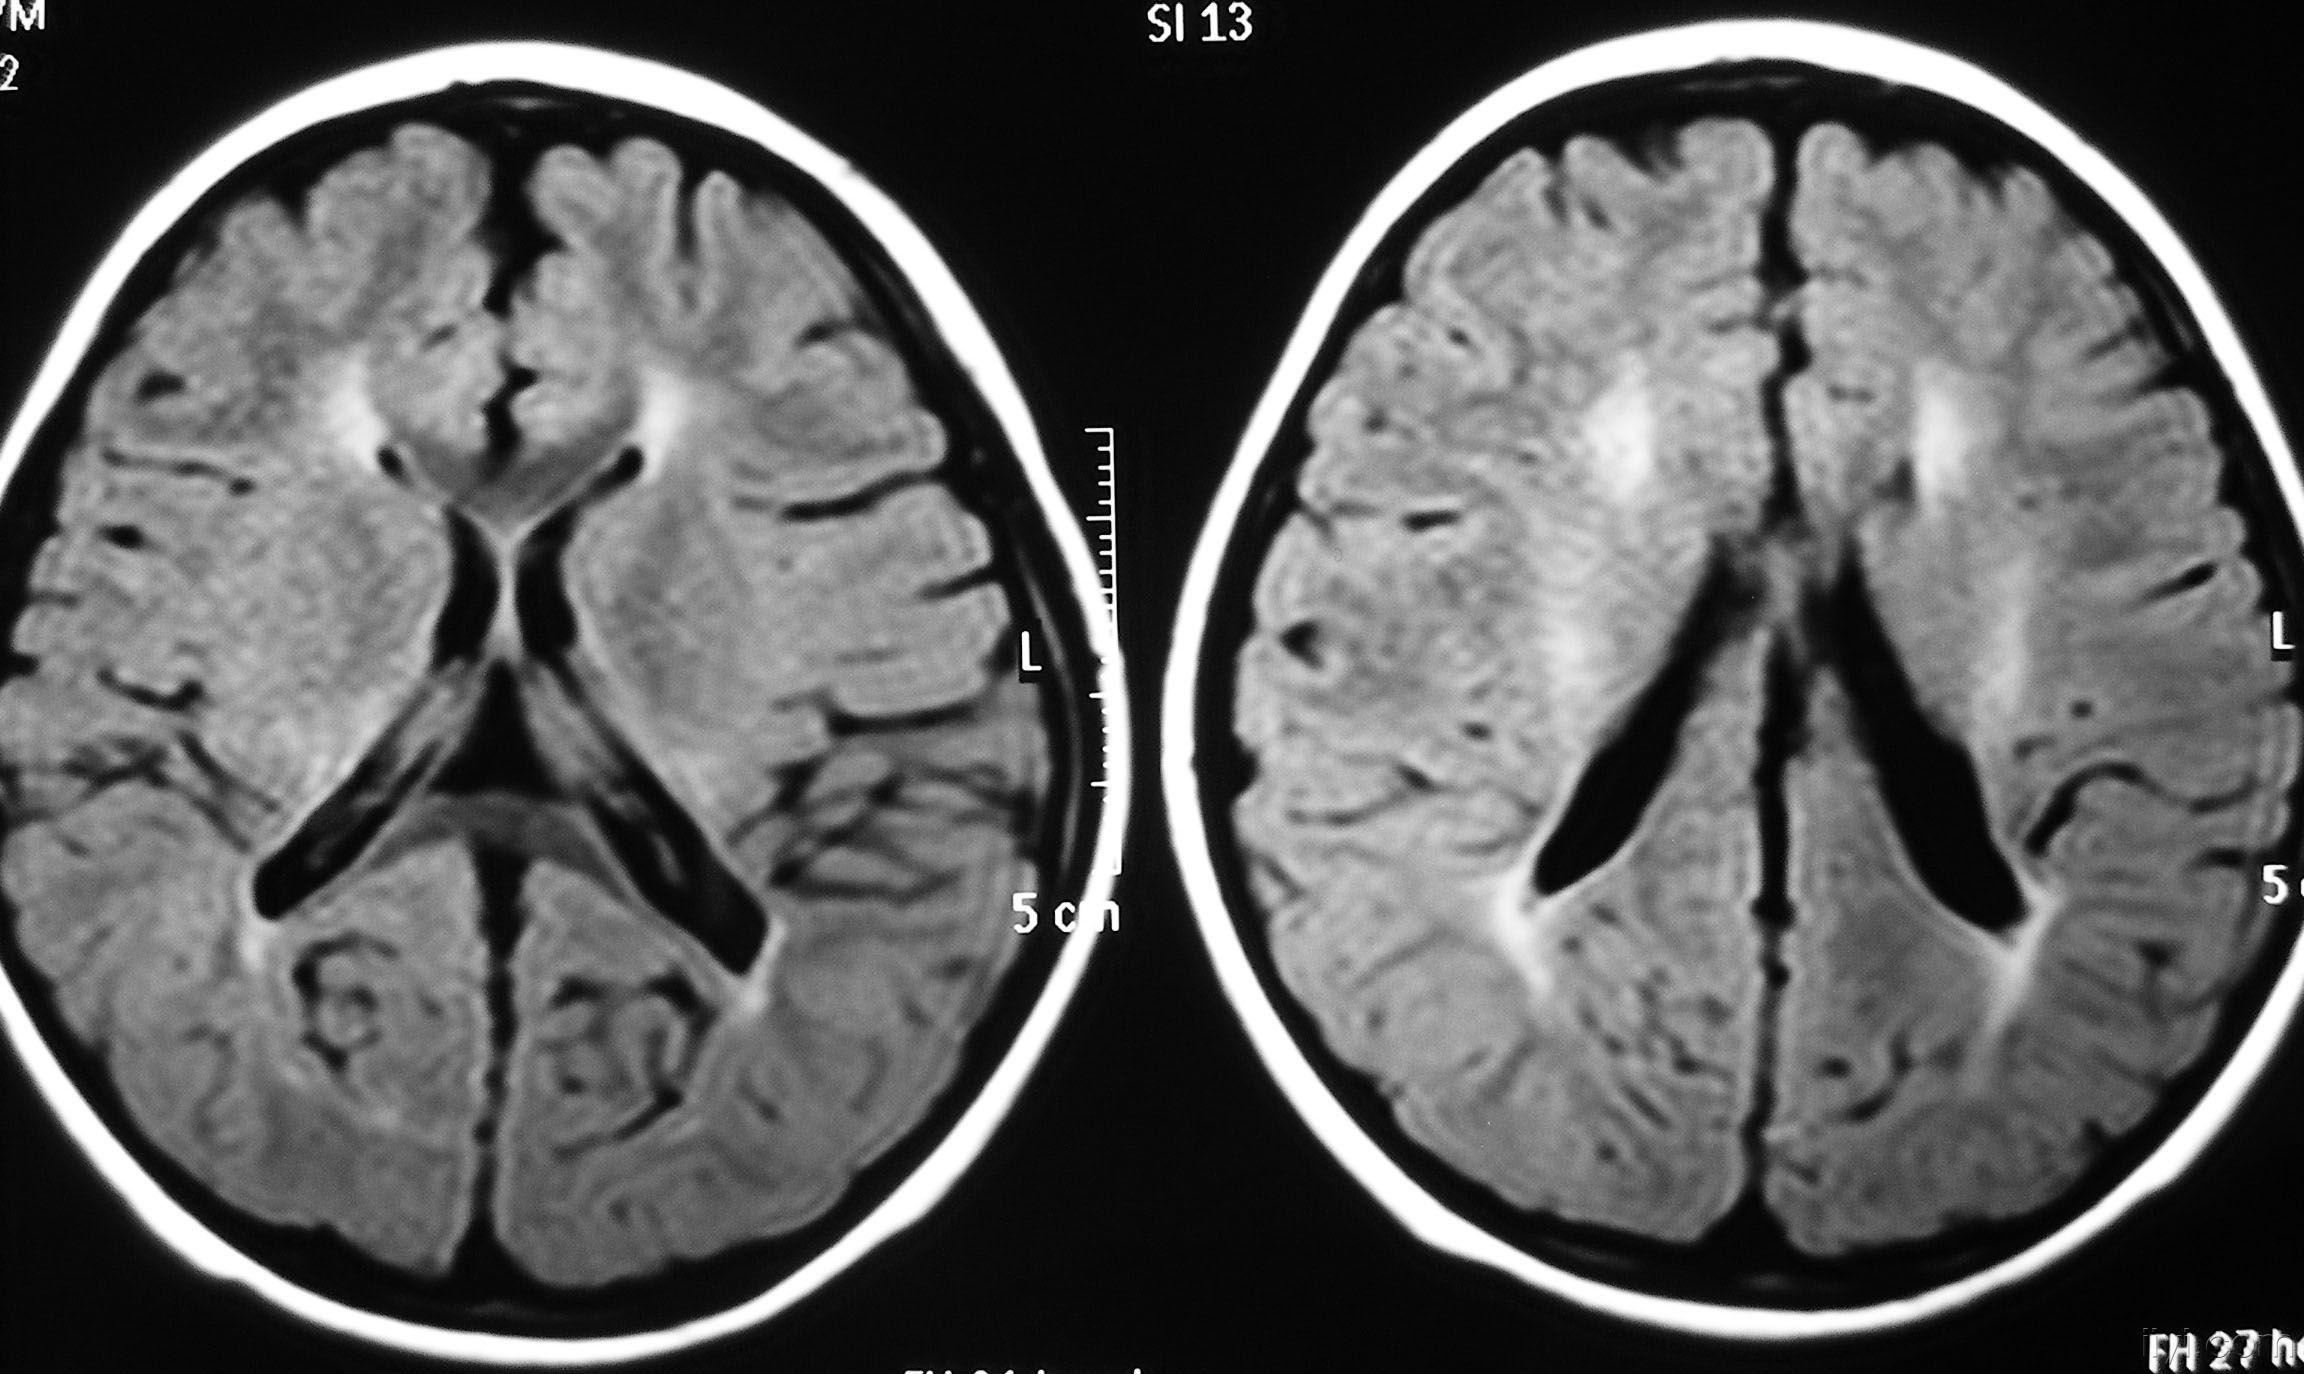

影像学发生于侧脑室周围,侧脑室扩大,脑白质减少。扩大的侧脑室外缘常不规则为其特点,多为双侧脑室同时扩大。脑白质减少,脑皮层与脑室侧缘相近。MRI T1呈低信号,T2呈高信号。